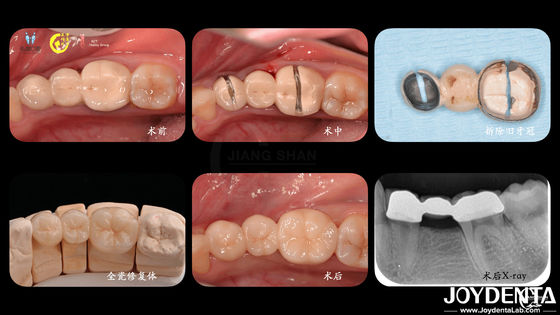

Kesinlikle uyumlu dişler Zirkonya diş taçları hassas üretim için CAD CAM sistemleriyle

CAD/CAM Uyumlu Zirkonya Diş Taçları Özel Tonlar ve Boyutlar İçin Hassas Üretim